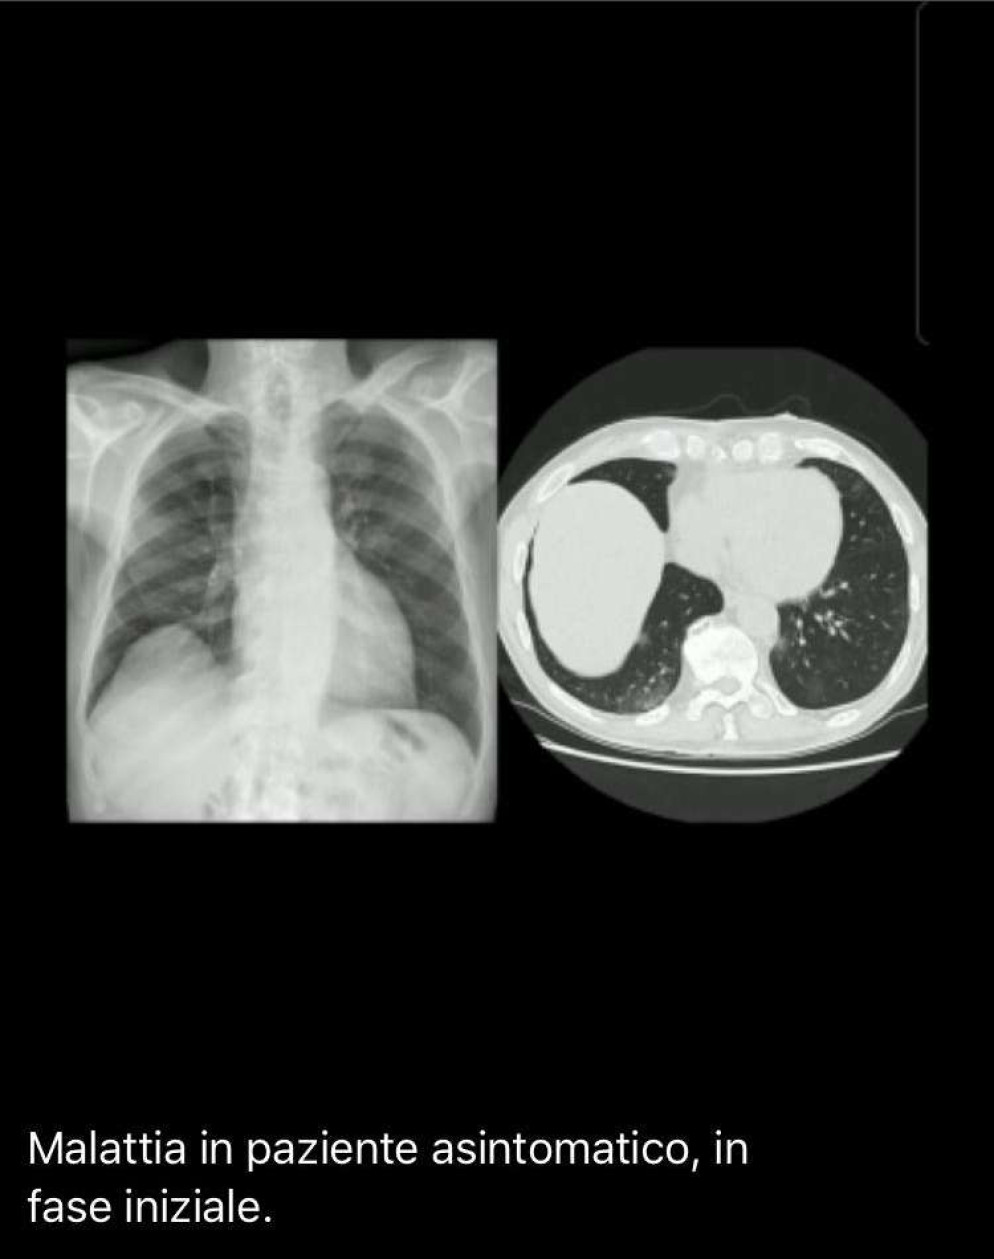

Un’invasione lenta e, purtroppo, talvolta inesorabile. Ecco come il coronavirus (SARS-CoV-2 o Covid-19) aggredisce i nostri polmoni e, in alcuni casi, i vasi polmonari. Lo si evince da alcune lastre che il direttore di Pneumologia dell’ospedale di Piacenza, Cosimo Franco, ha mostrato a “Libertà” per capire cosa accade durante la malattia.

La foto doppia “malattia in paziente asintomatico, in fase iniziale” mostra l’andamento dell’infezione in un paziente asintomatico, dunque nella fase iniziale. Il virus è rappresentato dalla massa di colore più biancastro che si osserva nella parte inferiore dei lobi dei polmoni. A fianco l’andamento della malattia nei polmoni nello stesso istante, ma vista dall’alto.